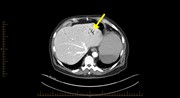

Chronic tubo-ovarian abscess complicated by hepatic portal venous gas

A rare occurrence of hepatic portal venous gas in a patient with chemotherapy-induced enterocolitis: the rise of benign aetiologies